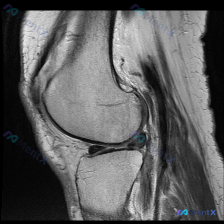

看到这个病例挺有代表性的,临床怀疑膝关节软骨异常,但只拿到了单一矢状位T1加权MRI,整理了完整分析思路分享给大家。

这是一份膝关节矢状位T1加权MRI的读片请求,核心疑问是:影像中是否存在可识别的软骨异常?目前无其他临床病史、体征或其他序列影像提供。

先整理一下现有影像的客观发现:

- 骨结构:股骨远端、胫骨近端、髌骨轮廓清晰,皮质连续,骨髓腔信号均匀,无明显异常信号或骨质破坏

- 半月板:形态完整,信号均匀低信号,无异常高信号穿透关节面,无明显撕裂移位

- 韧带:后交叉韧带、前交叉韧带走行自然,连续性良好,信号无异常

- 肌腱:髌腱走行清晰,信号均匀,附着点无增厚水肿

- 关节软骨:股骨髁、胫骨平台表面软骨厚度均匀,轮廓光滑,信号无明显异常

- 关节腔:无明显积液积聚,无滑膜增厚

基于现有影像,首先直接回答核心问题:当前T1序列未发现明确的结构性软骨异常,也没有发现其他明显的关节内病理性改变。但重点在于,这个结论是有条件限制的,咱们接着分析。